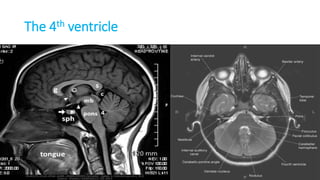

THE VENTRICLES

Ventricles

• Lateral ventricle

• Frontal horn

• Occipital horn

• Temporal horn

• Third ventricle

• Fourth ventricle

• Central canal

Foramen monoro

Aqueduct of Silvius

Interventricular foramina

(or foramina of monro)

The lateral ventricle

The frontal horn

The

occipital

horn

The temporal horn

The 3rd ventricle

The 4th ventricle

Foramen Luschka and Magendie